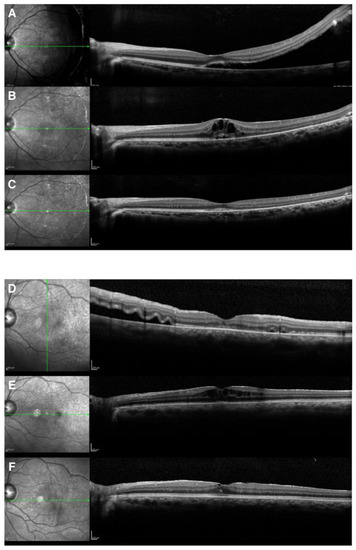

Surgery was performed by 4 retinal surgeons (M. Ishida, A. Takeyama, Y. Imamura, or Y. Ichikawa). Retinal breaks were identified in all patients and were treated with transscleral cryotherapy. Scleral buckling surgery was performed using silicon exoplants. Cryotherapy was used in all the patients to close retinal breaks, and diathermy was not used in our institution. Intravitreal gas injection, mostly with air, was generally used in cases of upper retinal breaks, particularly when subretinal fluid remained between breaks and a buckle. Subretinal fluid drainage was performed in cases with much fluid where buckles could not effectively seal retinal breaks. Encircling was chosen in cases with multiple breaks, in which segmental buckles could not seal all. All surgeries were performed under retrobulbar anesthesia, and the patients mostly received the same postoperative medications for 3 months, including topical antibiotics and prednisolone acetate. Patients underwent examinations similar to the preoperative examinations at 1 week, 1 month, 3 months, and 1 year after scleral buckling surgery. BCVA was converted to the logarithm of the minimal angle of resolution (logMAR). CME was defined by the presence of cystic spaces in the outer nuclear layer, outer plexiform layer, and/or in the inner nuclear layer on OCT (Figure 1 and Figure 2), which was observed until 1 year after surgery.

Representative images of a case that underwent successful SB are shown in Figure 1. The final anatomical success rate was 100% either for cases only with scleral buckling surgery or cases both with scleral buckling surgery and vitrectomy. The postoperative logMAR BCVA was 0.08 ± 0.33 and was significantly improved in comparison with the preoperative value (p < 0.001).

Figure 1. A 32-year-old woman showed rhegmatogenous retinal detachment with a peripheral break (A) and was successfully treated with scleral buckling surgery (B).